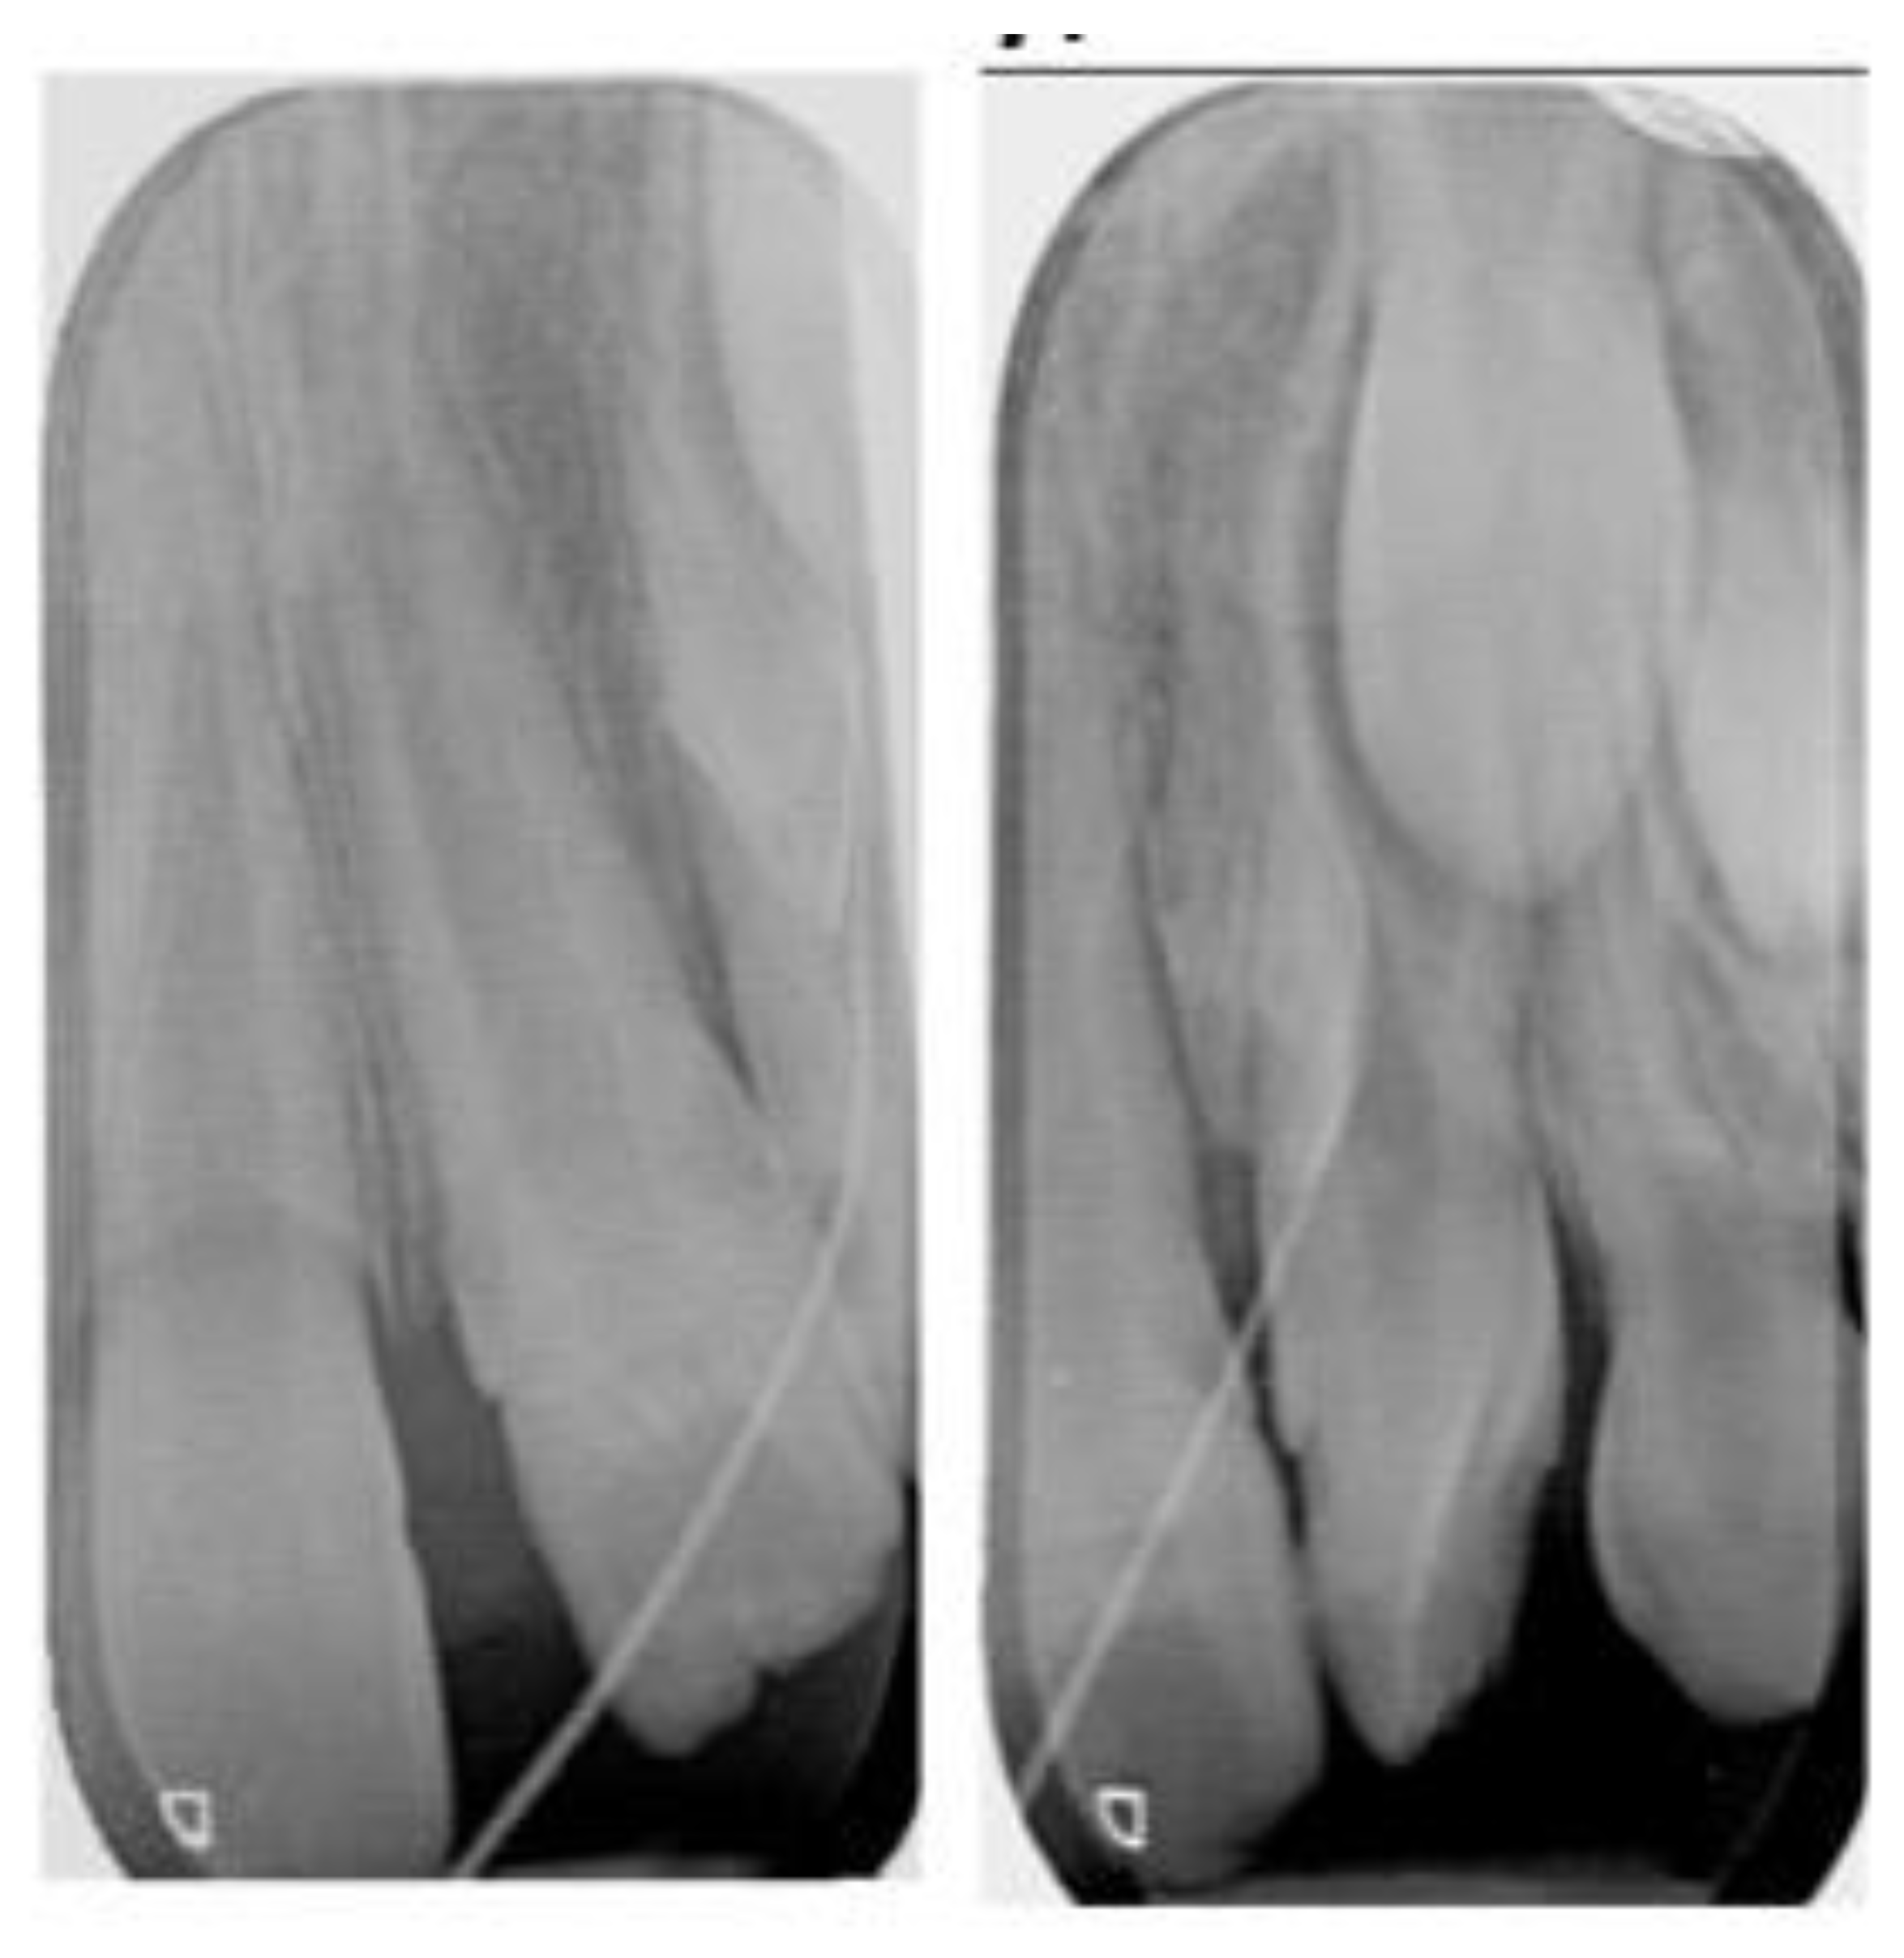

2.1. Clinical Examination and Diagnosis

2.2. Treatment Plan and Progress